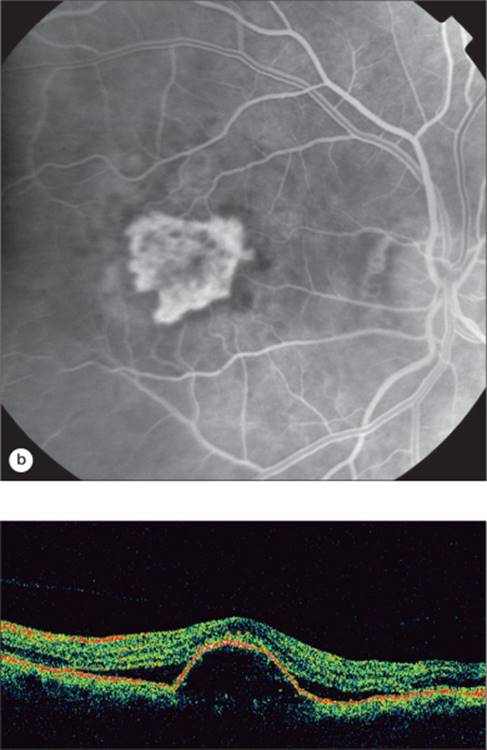

Exudative ARMD lesions are classified according to fluorescein angiography findings as either predominantly classic, minimally classic, or occult with no classic features. OCT findings do not necessarily correlate with the fluorescein classification. OCT demonstrates abnormalities in the retinal architecture in most cases of exudative AMD, with common findings of subretinal fluid, retinal thickening, pigment epithelial detachment, (Fig. 130.24) and choroidal neovascularization (CNV).[92] Occult CNV generally causes thickening of the RPE layer. The typical appearance with inability to distinguish the CNV from the RPE layer is termed type I (Fig. 130.22). This is by far more common. Classic CNV may have a similar appearance, or in some cases may break through Bruch's membrane and grow more clearly in the subretinal space (Fig. 130.23). This is termed a type II CNV. From a therapeutic perspective, this may influence the response to surgical therapy. A type II CNV complex would be more likely to respond to surgical removal without RPE damage, whereas removal of a type I membrane would be much more likely to damage the normal structure of the RPE and subsequently result in poor visual acuity. This was demonstrated in the Submacular Surgery Trial.[93,94]

FIGURE 130.22 OCT and corresponding fluorescein angiography of an occult choroidal neovascular membrane with a large amount of intraretinal fluid present. There is disruption and elevation of the RPE.

FIGURE 130.23 OCT and corresponding fluorescein angiogram of a classic CNV. Notice the discontinuity in the RPE/choriocapillaris band with a thick hyperreflective neovascular membrane in the subretinal space. There is accumulation of subretinal fluid as well as intraretinal fluid.